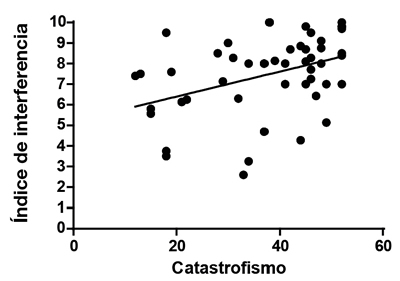

Se encontró una correlación lineal positiva moderada y estadísticamente significativa (R = 0,49, p = 0,0003) entre el valor de EVN y el catastrofismo total, una correlación lineal positiva moderada y estadísticamente significativa (R = 0,54, p < 0,0001) entre el índice de intensidad del dolor y el catastrofismo total (Figura 3), y una correlación lineal positiva moderada y estadísticamente significativa (R = 0,4, p = 0,004) entre el índice de interferencia del dolor y el catastrofismo (Figura 4).

Fig. 4. Correlación entre índice de interferencia y catastrofismo total. Esta correlación es positiva y moderada, estadísticamente significativa.